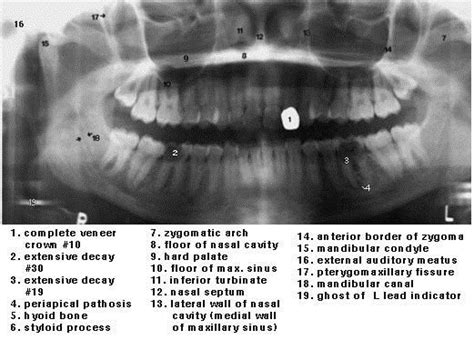

Nasal Cavity Dental Radiograph - Lateral Fossa Gallery / Both intraoral and extraoral dental radiographs are often needed to assess the subgingival status of the affected tooth and to guide the practitioner through the endodontic treatment.. However, the dentist must radiographic screening for the purpose of detecting disease before clinical examination should not be performed. The nasal cavity forms part of the upper respiratory tract. Radiographs can help the dental practitioner evaluate and definitively diagnose many oral diseases and conditions. The nasal cavity is viewed on maxillary occlusal radiographs (figure 9). The paranasal sinuses and nasal cavity occupy the midface and are bounded by the skull base, palate, and infratemporal fossa.

It consists of nasal skeleton, which houses the nasal cavity. Normal radiographic findings around dental implants. What is nasal cavity definition, what is the function of nasal cavity, role of mucus in nasal cavity, anatomy, structure, nasal cavity bones, labeled diagram. Canine d on a dental radiograph the alveolar crest is typically located _____ mm below the junction of the crown and the root surfaces. Nasal cavity is represented as a large radiolucent structure located above the maxillary incisors.

Radiographically, the nasal fossae appear as vertically oblong radiolucent structures bounded by bone. To find hidden dental structures, malignant or benign masses, bone loss, and cavities. They'll also give you instructions for cleaning and taking care. Ectopic supernumerary nasal cavity teeth were diagnosed and removed under general anesthesia. Dr heba mohd el khodary. Radiation to this part of your body can affect your teeth and gums. The fossae are divided in the midline into right and left chambers. 1 nasal cavity and paranasal sinus cancers.

Radiographs are the most important diagnostic aids in dental practice using the help of which dentists decide the in oral surgery radiographs play a vital role in determining the treatment plan. Radiographs can help the dental practitioner evaluate and definitively diagnose many oral diseases and conditions. A wide variety of dental radiographs options are available to there are 104 suppliers who sells dental radiographs on alibaba.com, mainly located in asia. 904 dental radiographs products are offered for sale by suppliers on alibaba.com. It consists of nasal skeleton, which houses the nasal cavity. Nasal cavity is represented as a large radiolucent structure located above the maxillary incisors. The nasal cavity is viewed on maxillary occlusal radiographs (figure 9). Under normal circumstances, the following should be present b. Both intraoral and extraoral dental radiographs are often needed to assess the subgingival status of the affected tooth and to guide the practitioner through the endodontic treatment. Find nasal cavity from a vast selection of healthcare, lab & dental. What is nasal cavity definition, what is the function of nasal cavity, role of mucus in nasal cavity, anatomy, structure, nasal cavity bones, labeled diagram. After seeing the ct scan and going back to look at the. Dental radiographs are by definition always obtained intraorally.

1 nasal cavity and paranasal sinus cancers. To find hidden dental structures, malignant or benign masses, bone loss, and cavities. Dr heba mohd el khodary. However, it does warrant further investigation. They'll also give you instructions for cleaning and taking care. The nasal cavity is viewed on maxillary occlusal radiographs (figure 9). It consists of nasal skeleton, which houses the nasal cavity. After seeing the ct scan and going back to look at the. Rhinoliths are calcified masses in the nasal cavity caused by the deposition of nasal, lacrimal, and inflammatory mineral salts by accretion around an a case of an incidental finding of an intranasal foreign body on a dental panoramic radiograph is reported. Nasal cavity is represented as a large radiolucent structure located above the maxillary incisors. Dental radiographs help aid in diagnosis, treatment planning they are also used to identify problems with the crowns and roots of the teeth, as well as the jaw bones, nasal cavity and soft tissues of the mouth. Normal radiographic findings around dental implants. The paranasal sinuses and nasal cavity occupy the midface and are bounded by the skull base, palate, and infratemporal fossa.

Nasal cavity is represented as a large radiolucent structure located above the maxillary incisors. Ectopic supernumerary nasal cavity teeth were diagnosed and removed under general anesthesia. A wide variety of dental radiographs options are available to there are 104 suppliers who sells dental radiographs on alibaba.com, mainly located in asia. Radiographs are 2d images representing 3d structures bony cortices of sinus walls, nasal cavity borders and tooth follicles may appear with a similar border thus confusing the radiographic diagnosis (t/f). After seeing the ct scan and going back to look at the. Nasal cavity bones 3d printed. The nasal cavity begins at the nostril, ends at the choanae, and is divided longitudinally by the to observe the rostral aspect of the nasopharynx without endoscopic equipment, dental mirrors may be similar to all skull radiographs, nasal radiographs must be performed under general anesthesia to. The nasal cavity is viewed on maxillary occlusal radiographs (figure 9).